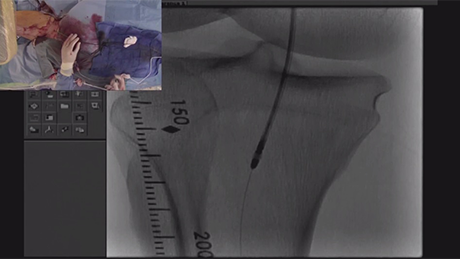

Pre-procedure CTO of right distal SFA/proximal popliteal Pre-procedure CTO of right distal SFA/proximal popliteal

Final angiogram: post-Jetstream atherectomy and adjunctive PTA Final angiogram: post-Jetstream atherectomy and adjunctive PTA